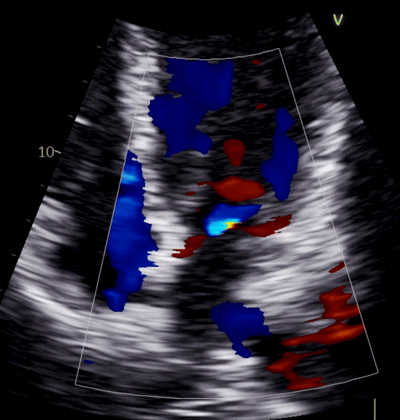

Echocardiograms in Greater Portland & Downeast Maine

Quick echocardiogram appointments across Maine — cardiologist-interpreted results sent to your provider within 48 hours. Insurance accepted, or self-pay for just $450.

• Complete transthoracic echocardiogram performed by certified sonographers

• Cardiologist interpretation